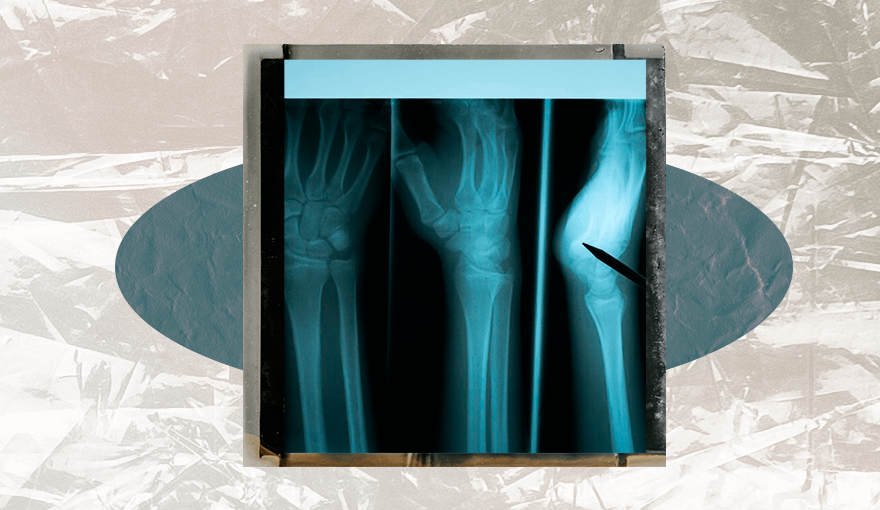

1. Остеопороз может вызвать переломы костей

Кости, пораженные остеопорозом, становятся более хрупкими. Поэтому вероятность переломов сильно увеличивается. Если сломаешь кость из-за несерьезного падения, которое обычно не приводит к подобным травмам, это повод пройти обследование.

Остеопороз может вызвать переломы костей из-за подъема тяжестей, сгибания корпуса, сильного кашля или прыжков.